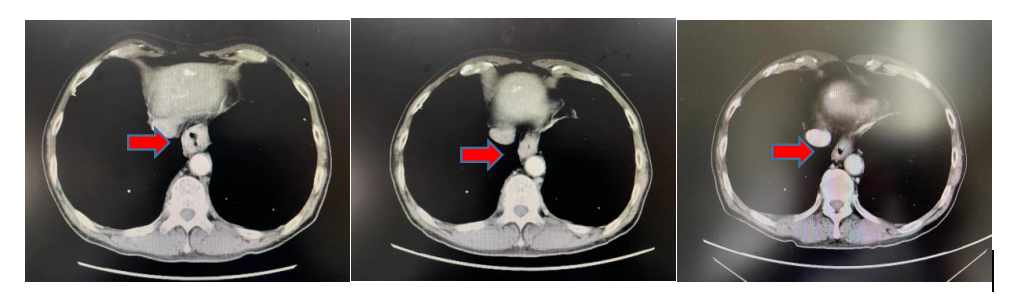

放疗前,放疗中,放疗后增强CT对比图像

患者男性,70岁,多年慢性阻塞性肺疾病史,饮酒30余年。2022年3月因进食梗阻进行性加重就诊于我院,行胃镜检查示:距门齿38-40cm处可见管腔变窄,环周浸润,并可见约1.0×1.0cm隆起性病变,表面粗糙不平。活检3块,质脆,送检,病理示:(食管下段-贲门)低分化腺癌。行胸部增强CT提示:食管下段管壁增厚,贲门区不均增厚,境界不清,增强后呈明显不均强化,相应管腔变窄,周围脂肪间隙显示不清,符合贲门癌表现。目前诊断为:P食管下段-贲门癌cT3N0M0ⅡA期。